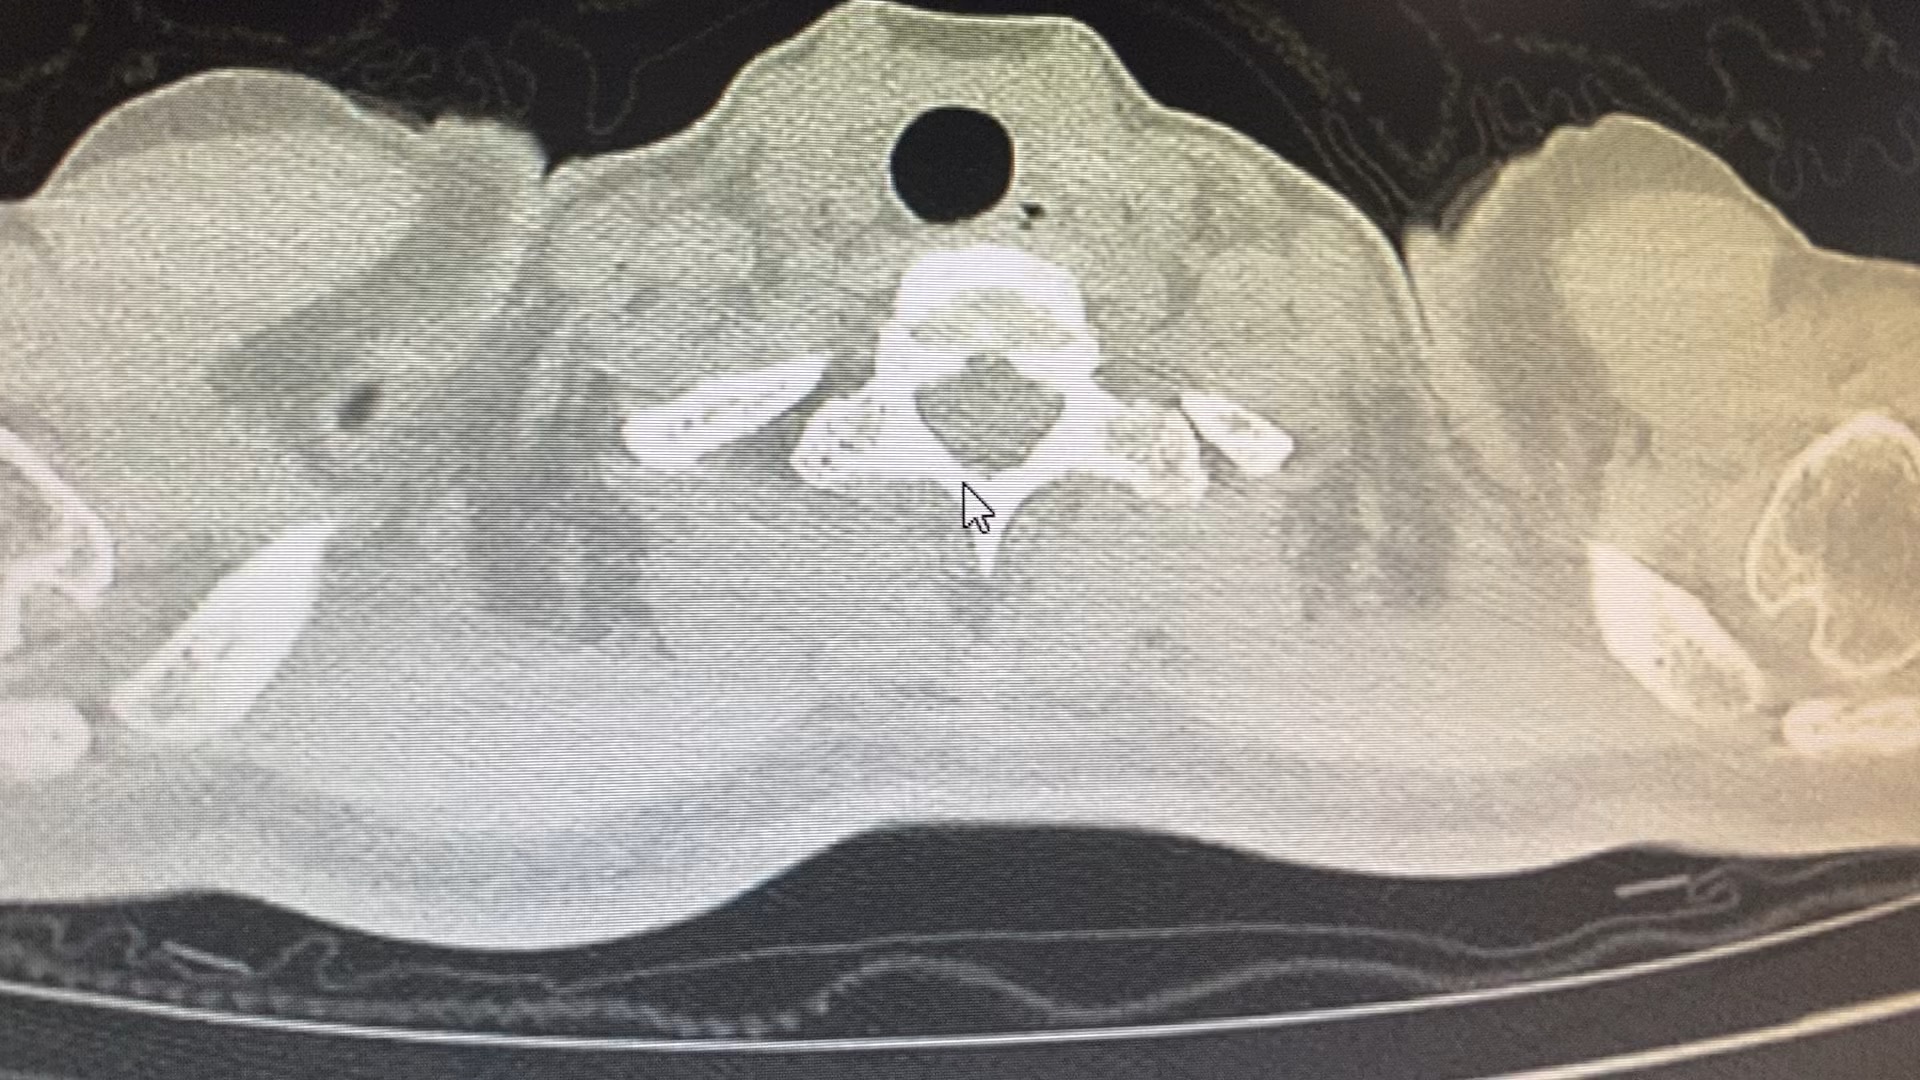

患者女,32岁,咳嗽咳痰2月入院。患者2月前开始无明显诱因出现咳嗽咳痰,无发热,畏寒寒战,盗汗,无胸闷气急等。

看ct考虑什么病原菌感染?